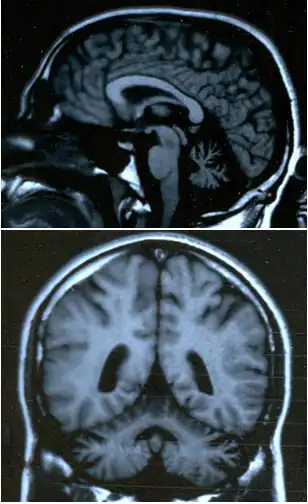

Ataxia (do grego ατάξις, sem coordenação), ou distaxia, é um transtorno neurológico caracterizado pela falta de coordenação de movimentos musculares voluntários e de equilíbrio. É normalmente associada a uma degeneração ou bloqueio de áreas específicas do cérebro e cerebelo.

- Ataxia cerebelar: Causada por danos às vias cerebelares, resultam na perda de coordenação motora e planejamento dos movimentos. Os sintomas dependem da área do cerebelo afetada.

O cerebelo é responsável por uma série de comandos centrais tendo papel de destaque na elaboração, aprendizagem e execução da motricidade. Os possíveis sintomas incluem: